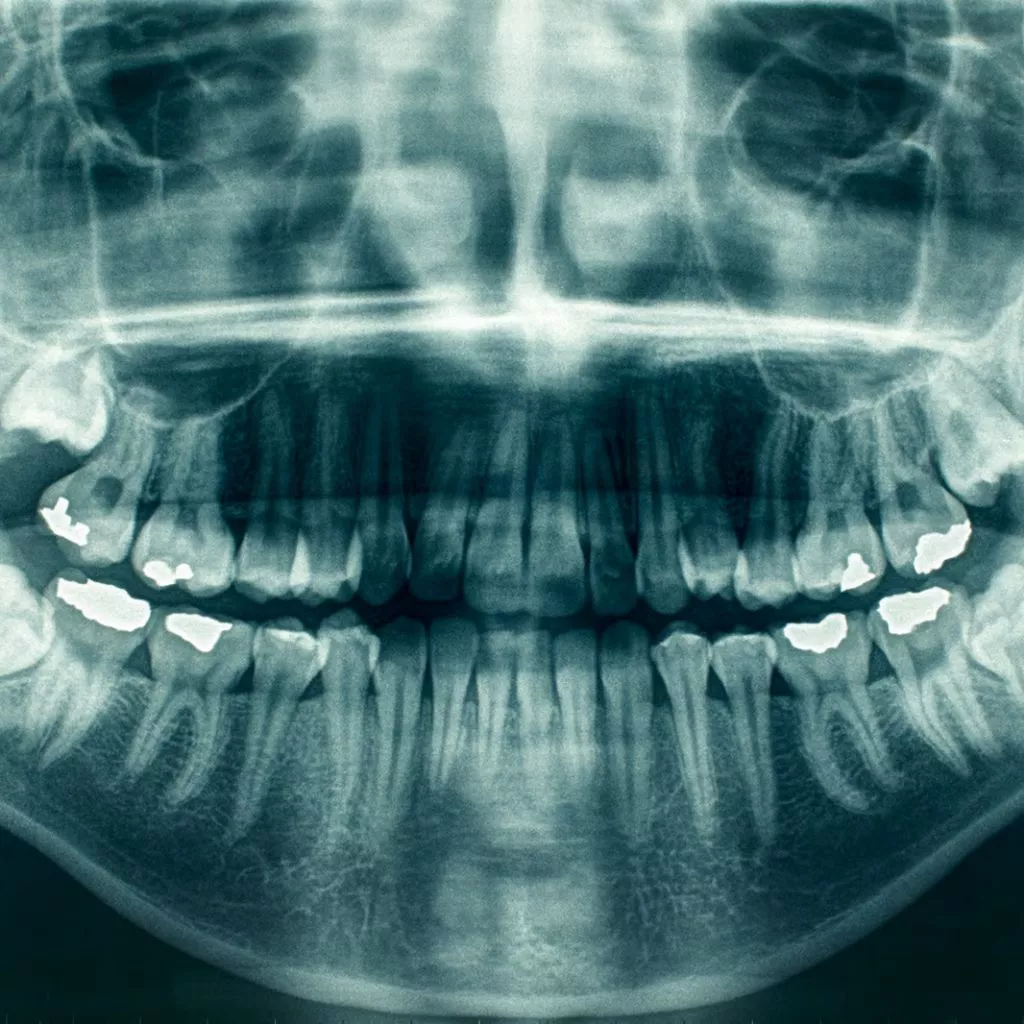

At Channel Islands Family Dental, we use cutting-edge intraoral dental imaging to deliver precise and detailed evaluations of your oral health. This advanced technology enables us to capture high-quality images of your teeth and gums, allowing for accurate and personalized treatment plans. Visit our locations in Oxnard, Santa Paula, Ventura, Newbury Park, and Port Hueneme to discover how intraoral dental imaging can improve your dental care experience.